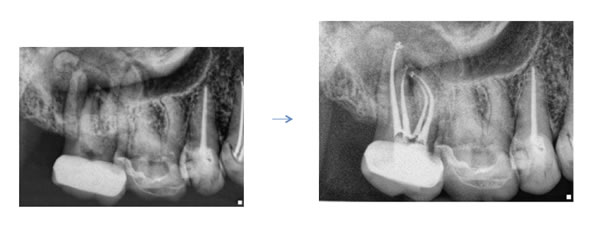

Case by Dr. Michael Sherman

Time? Many times a root canal on an upper first molar will take me nearly two hours to complete. A lot of this time is focused on finding and instrumenting the ML canal. Make sure you give yourself ample time so that you can treat the tooth without feeling the need to rush.